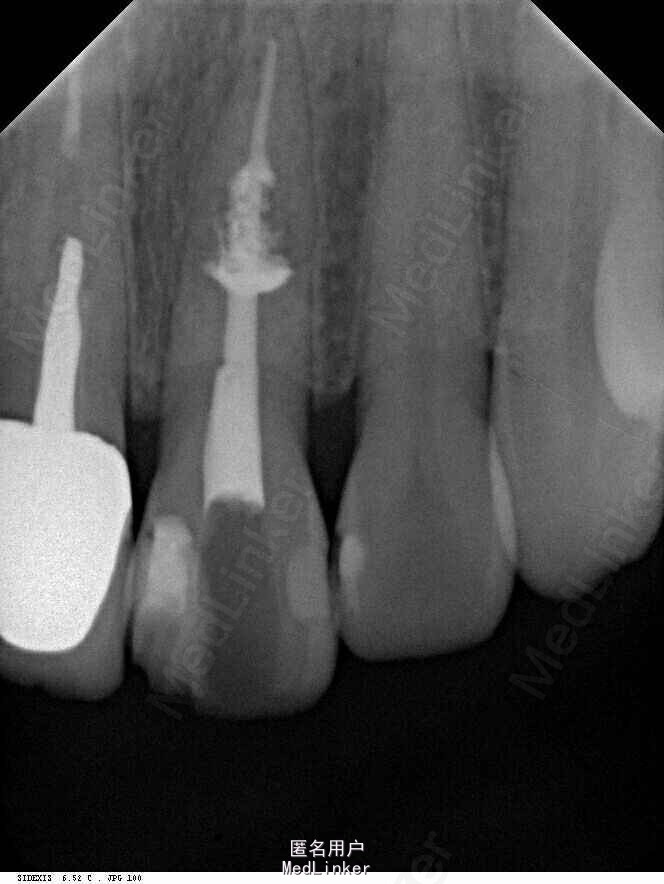

诊断:左上中切牙牙根内吸收。治疗计划:左上中切牙根管治疗,全冠修复。 治疗过程:患者知情同意。使用含1/100,000肾上腺素的4%盐酸阿替卡因(碧兰麻,艾龙)局部浸润麻醉,橡皮障隔湿。去腐未尽露髓,露髓孔出血多。开髓,使用10#不锈钢K锉(MANI,日本)探查根管,根管中段有钙化物阻挡,不能达到牙根全长(图3A)。在显微镜下(Leica M400E,莱卡, 德国) 使用超声尖(E1根管治疗超声尖,啄木鸟公司,中国)通开,采用根管长度测量仪(Root ZX, Morita公司,日本)加诊断丝片法(图1B)测量根管长22 mm。使用控制扭矩马达(X-smart,登士柏)和镍钛旋转器械(Hero 642, Micromega)根管预备,根管预备过程中使用5.25%次氯酸钠溶液冲洗。 根备完成后使用超声荡洗根管,5.25%次氯酸钠溶液3 分钟, 17% EDTA溶液1分钟。干燥根管,使用螺旋充填器根管内封氢氧化钙糊,氧化锌丁香油水门汀暂封。1周后患者复诊,患者述无术后不适,检查暂封完好,无叩痛,不松,牙龈无红肿瘘管。使用橡皮障隔湿,去除暂封物,超声荡洗根管,5.25%次氯酸钠溶液3 分钟, 17% EDTA溶液1分钟。干燥根管,牙胶尖(达雅鼎,中国)和必兰根充糊剂(Cortisomol, 艾龙公司,法国)热垂直加压法根管充填。术后片显示根充恰填,可见牙胶/糊剂被压入钙化物周围和内部缝隙内